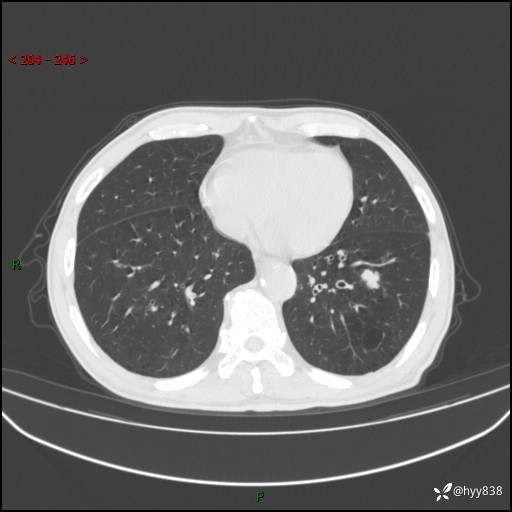

辅助检查:CT

增强动脉期+静脉期

各期CT值:38Hu 52hu 55hu